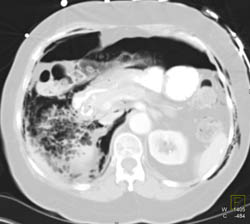

Pancreatic Cancer Encases the PV/SMV With Liver Metastases